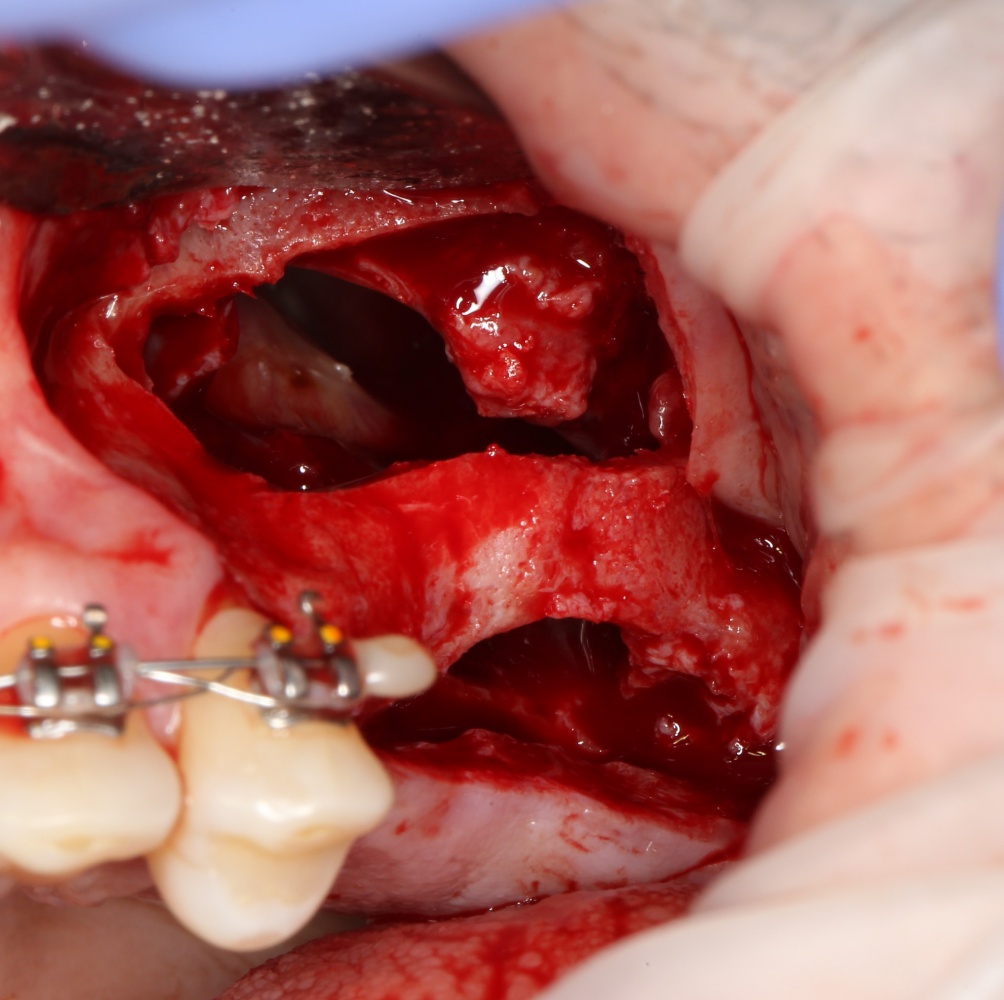

Скелетирование и создание доступа.

Наперво, мне нужно удалить разрушенный зуб и получить костный аутотрансплантат.

Для получения костного блока, мы открываем донорскую зону, наружную косую линию нижней челюсти.

Получение костного аутотрансплантата.

Здесь потребуется пародонтологический зонд с миллиметровой разметкой или какой-то другой измерительный прибор (операционная линейка). Ранее по КЛКТ я измерил костный дефект, теперь нужно нанести границы будущего костного блока на донорскую зону.

Для получения костного блока мы использовали ультразвуковую пьезохирургическую систему. Это самый удобный и безопасный инструмент для проведения подобных манипуляций. С помощью него мы сформировали и выделили костный блок. Он должен отделяться легким движением остеотома или элеватора. Как это сделать правильно — читай здесь>>